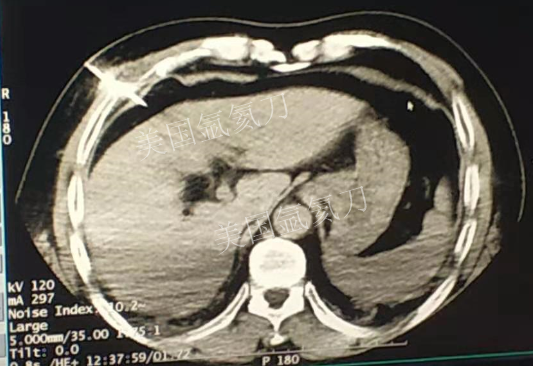

59岁男性肝部氩氦刀手术治疗

发布人:美国氩氦刀技术官方网站    发布时间:2019/3/13 15:42:57